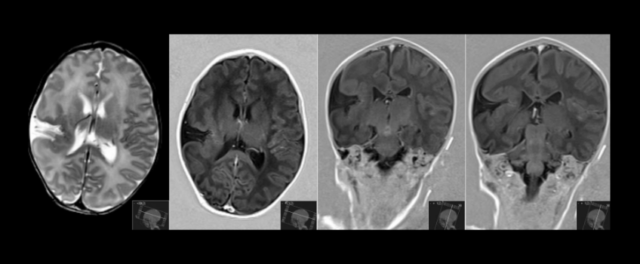

Diagnosticul se poate pune numai pe o investigație imagistică a creierului: tomografie computerizată sau rezonanță magnetică. Afecțiunea apare ca o “despicătură” în creier, care se întinde de la suprafața acestuia până la ventriculii laterali (cavitățile cu lichid din mijlocul creierului).

Diagnosticul se stabilește pa baza de CT cerebral sau RMN cerebral, când se pot identifica și alte malformații cerebrale. Nu există un test genetic specific pentru aceasta boală.